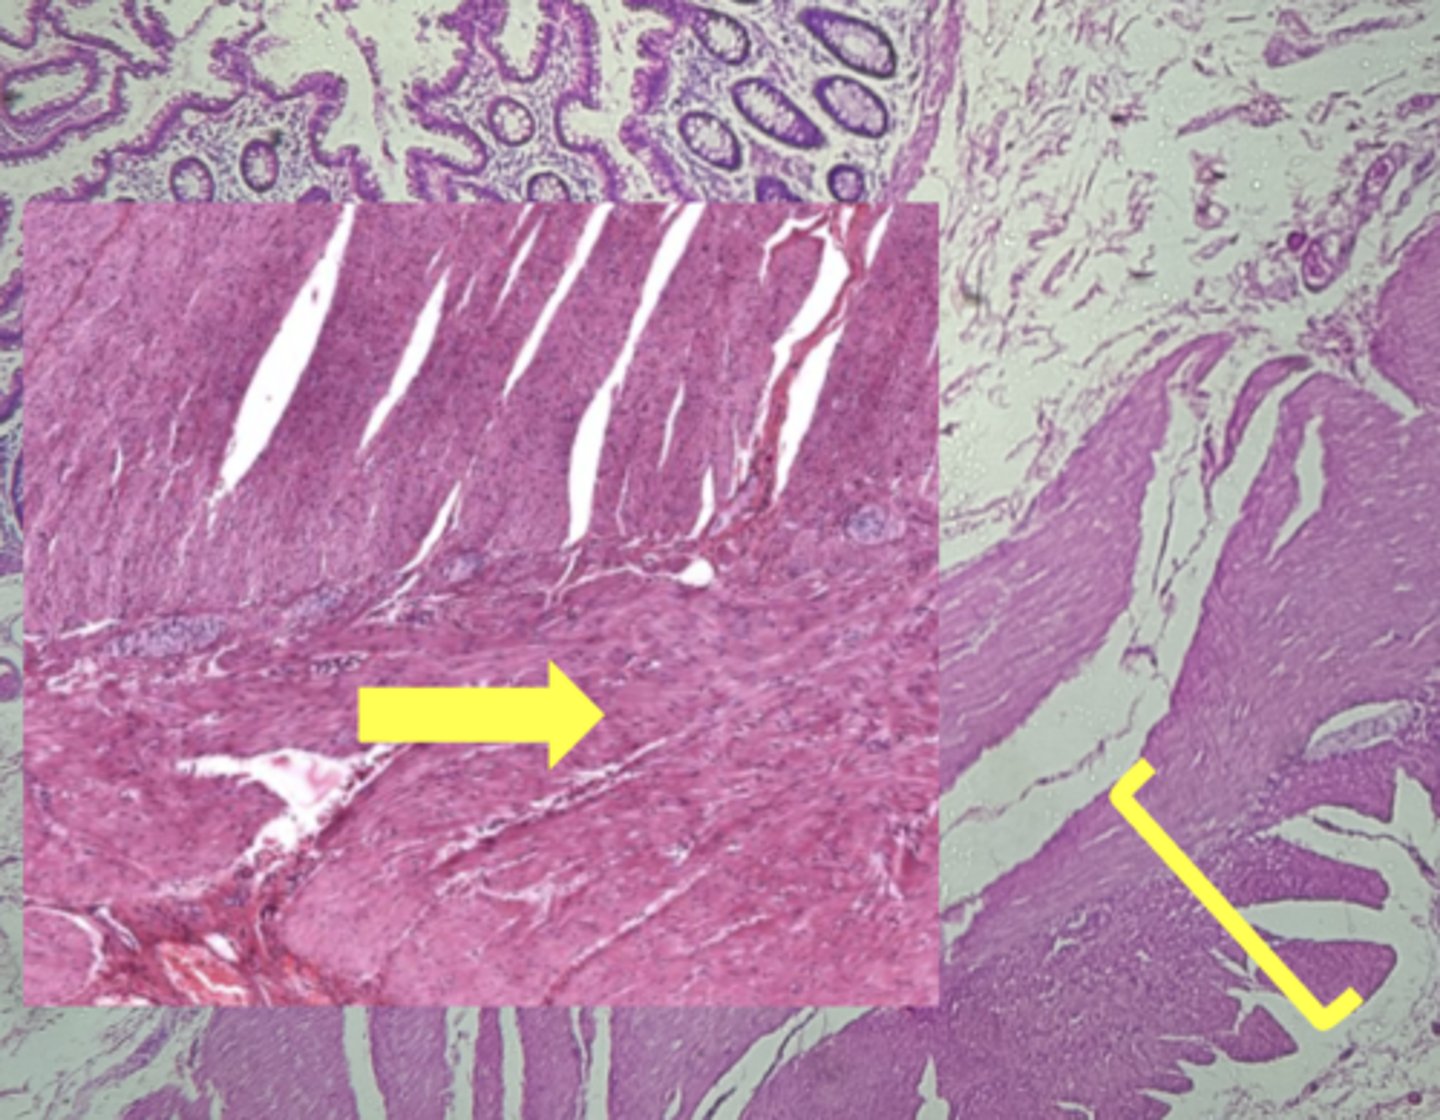

stomach

name the tissue

muscularis externa (3 LAYERS-KEY CHARACTERISTIC)

(stomach)

oblique layer

circular layer

longitudinal layer

simple columnar epithelium

gastric pits (KEY CHARACTERISTIC)

gastric glands (KEY CHARACTERISTIC)